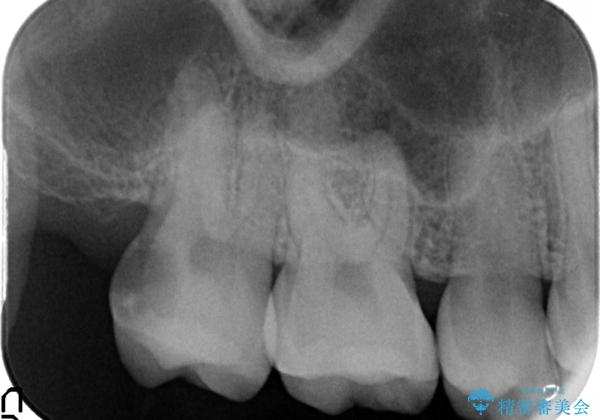

- 右上7の虫歯が大きく、他院にて抜歯と言われたが、なんとか残せないかと当院にいらっしゃった方の症例です。

自発痛の既往および持続痛を認めたため、カリエス除去後根管治療を行いました。

その後オールセラミッククラウンによる補綴を行いました。

- オールセラミッククラウン…¥100,000、仮歯…¥10,000、ファイバーコア…¥20,000費用は治療当時の料金となります